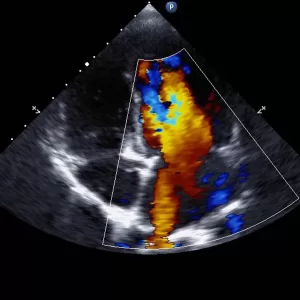

Ecocardiografia – confirmă îngustarea valvei aortice, calcifierea acesteia. Măsoară gradientul transvalvular.

Stadializarea severității stenozei aortice se face în principal pe baza ecocardiografiei Doppler și a cateterismului cardiac: